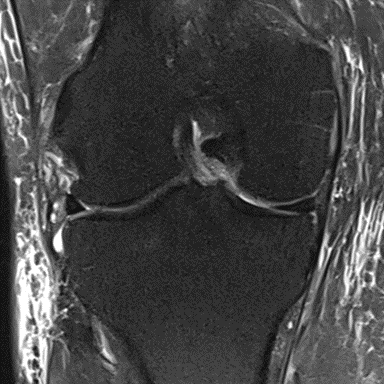

MRI scans illustrating the improvements regarding Group 2 are presented below, showing pre-treatment images with evident cartilage defects, pronounced bone marrow edema, and synovial inflammation, followed by post-treatment scans demonstrating improved joint structure, reduced edema, and decreased inflammation (Figures 12-29).

MRIs of Group 2

Figure 16: Female, 76 years, pre-intervention MRI.

Figure 17: Female of figure 16, two-month follow-up MRI: MSC plus ChondroFiller® liquid.